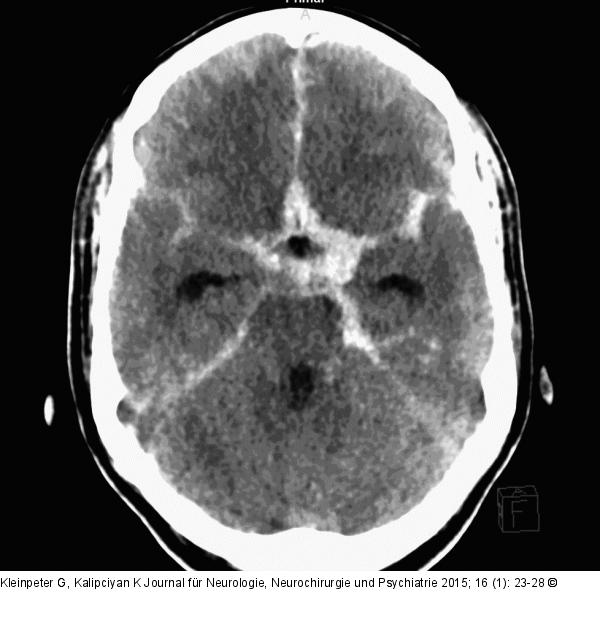

Abbildung 1: Subarachnoidalblutung Aneurysmatische Subarachnoidalblutung (aSAB). |

Aneurysmatische Subarachnoidalblutung (aSAB). |